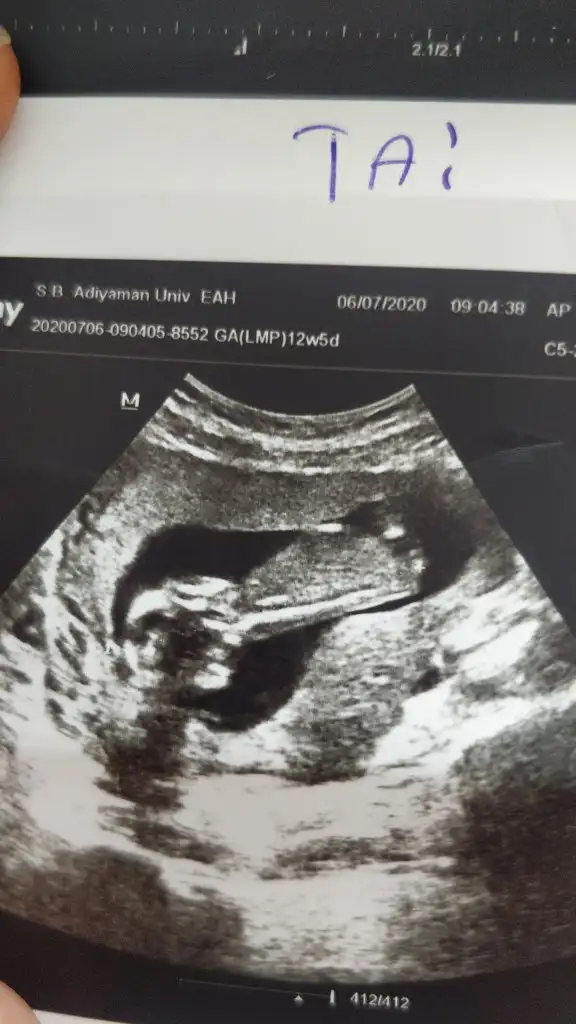

İnşallah Rabbim sağlıklı evlat nasip etsin.baska USG yok ama Perşembe günü gideceğim doktora o zaman verdiginde yine paylaşırımKız sanki emin olamadım başka usg de paylaşın

11 12 13 hafta olmalı cnmIkra meyra 15 haftalık bacakları kapalıydı. Erkeğe benzetti doktor. Sizdende bir tahmin alabilir miyim :)Eki Görüntüle 2655284